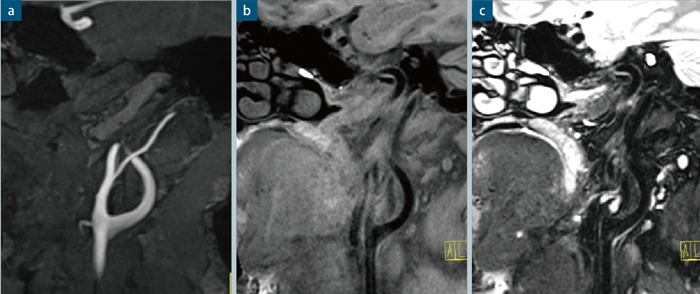

●症例1 頭部MRA像

MRA,TR/TE:22/3.91,スライス厚:0.4mm(iso voxel),マトリックス:1024×768,撮像時間: 8分,iPAT factor:3

●症例3 頸部プラーク撮像

MPR像。T1,T2強調画像ともにスピンエコータイプのSPACE法を用いている。いずれも三次元撮像を行っており,検査終了後に自由なスライス面を再構成して確認できる。

a:MRA,TA:5min,空間分解能:0.5mm iso voxel

b:SE Type,T1 SPACE,FS,TA:3min,空間分解能:0.8mm iso voxel

c:SE Type,T2 SPACE,FS,TA:3min,空間分解能:0.8mm iso voxel